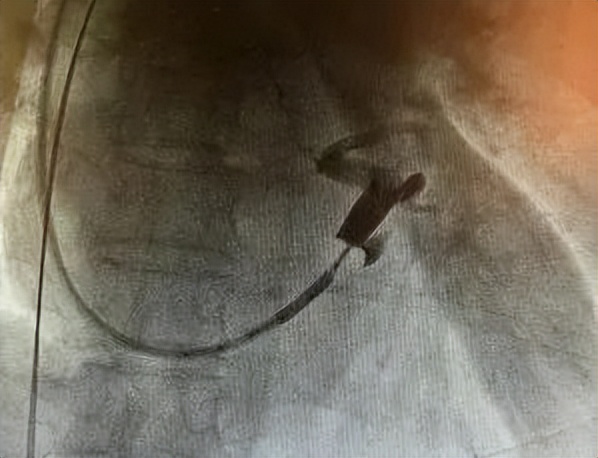

冠脉静脉造影

术中,成功将三个电极植入到右心房、右心室、左心室(冠状静脉分支远端)。